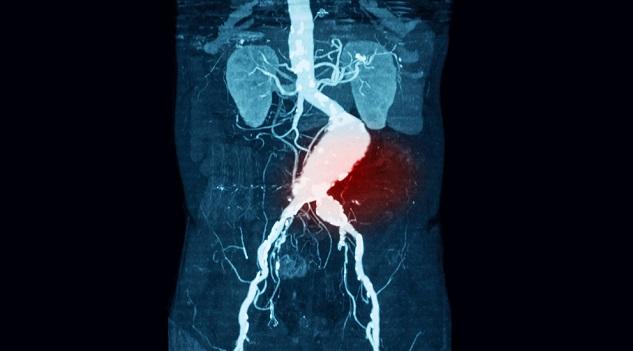

BARCELONA, Spain—An ambitious trial looking at population-based screening for abdominal aortic aneurysm (AAA), peripheral artery disease, and hypertension in men was associated with a significant reduction in all-cause mortality and should prompt policy makers to consider implementing such programs, researchers said here at the European Society of Cardiology Congres 2017.

Screening was conducted by nursing teams equipped with portable ultrasound scanners, bedside cholesterol measurement devices, portable Dopplers, and blood pressure monitors. AAAs were detected in 680 men (3.6%), of which 61 were 5.5 cm or larger. Peripheral artery disease was detected in 2,052 (10.9%) and hypertension in 1,962 (10.5%). Sixty patients found to have AAA of at least 55 mm in size; eight opted not to undergo repair.